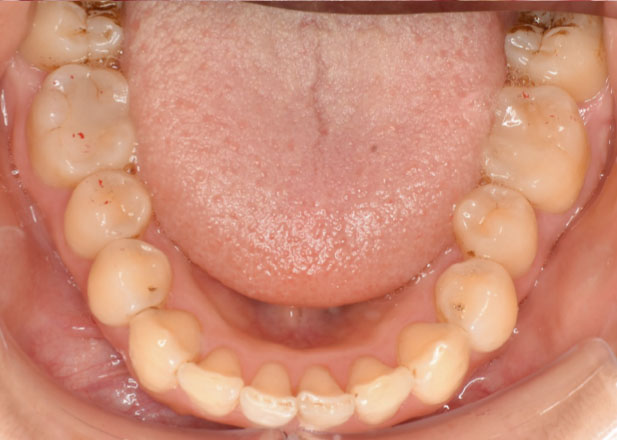

治療前

マウスピース矯正 マウスピース矯正 マウスピース矯正

口腔内写真